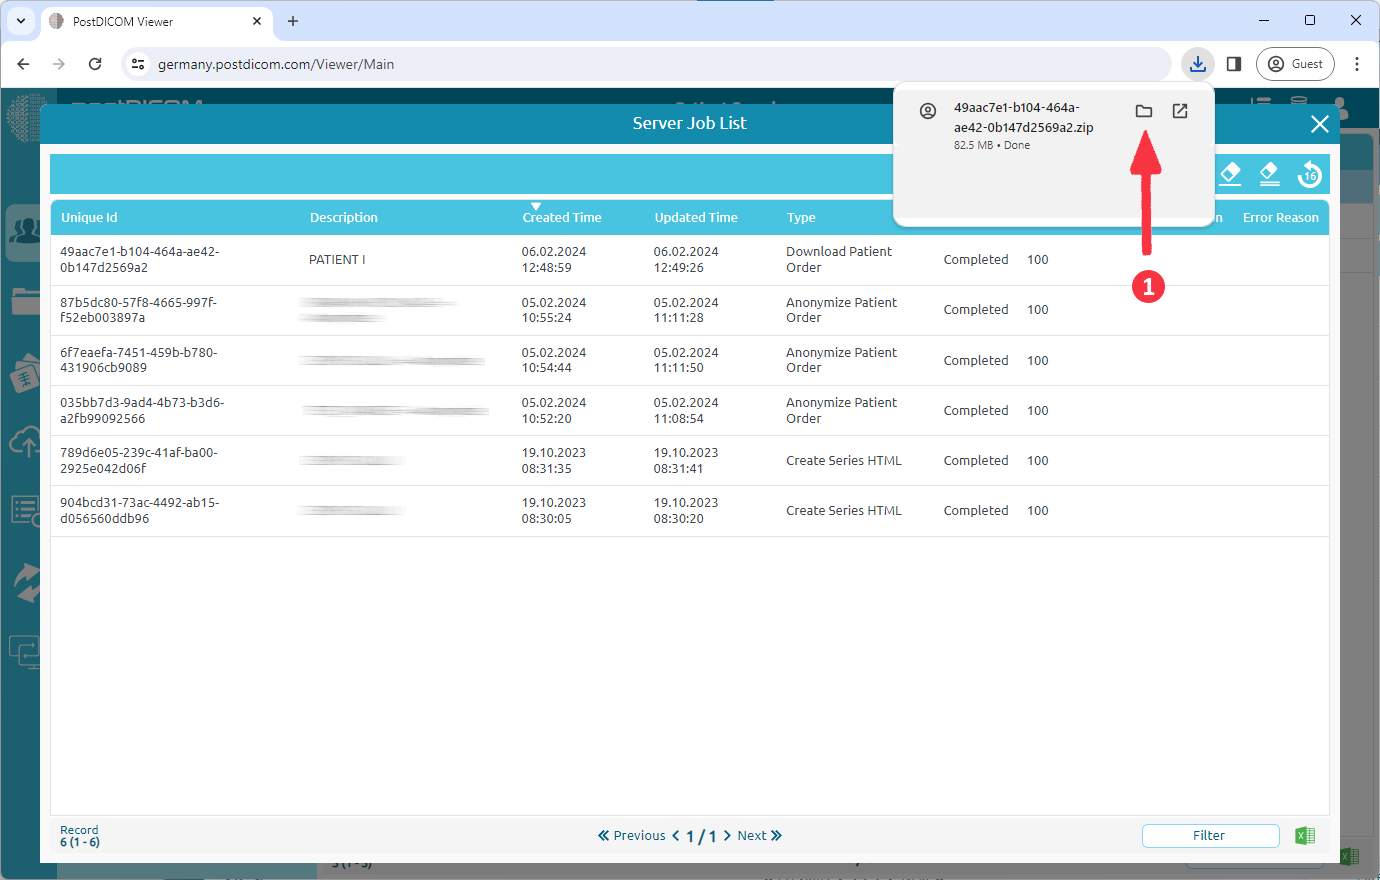

A job which type is 'Download Patient Order' has been added to your job list. When the job is complete, the download will start automatically. If it does not start, you can click the 'Download' button (1).

Click the folder icon (1) to view downloads folder.